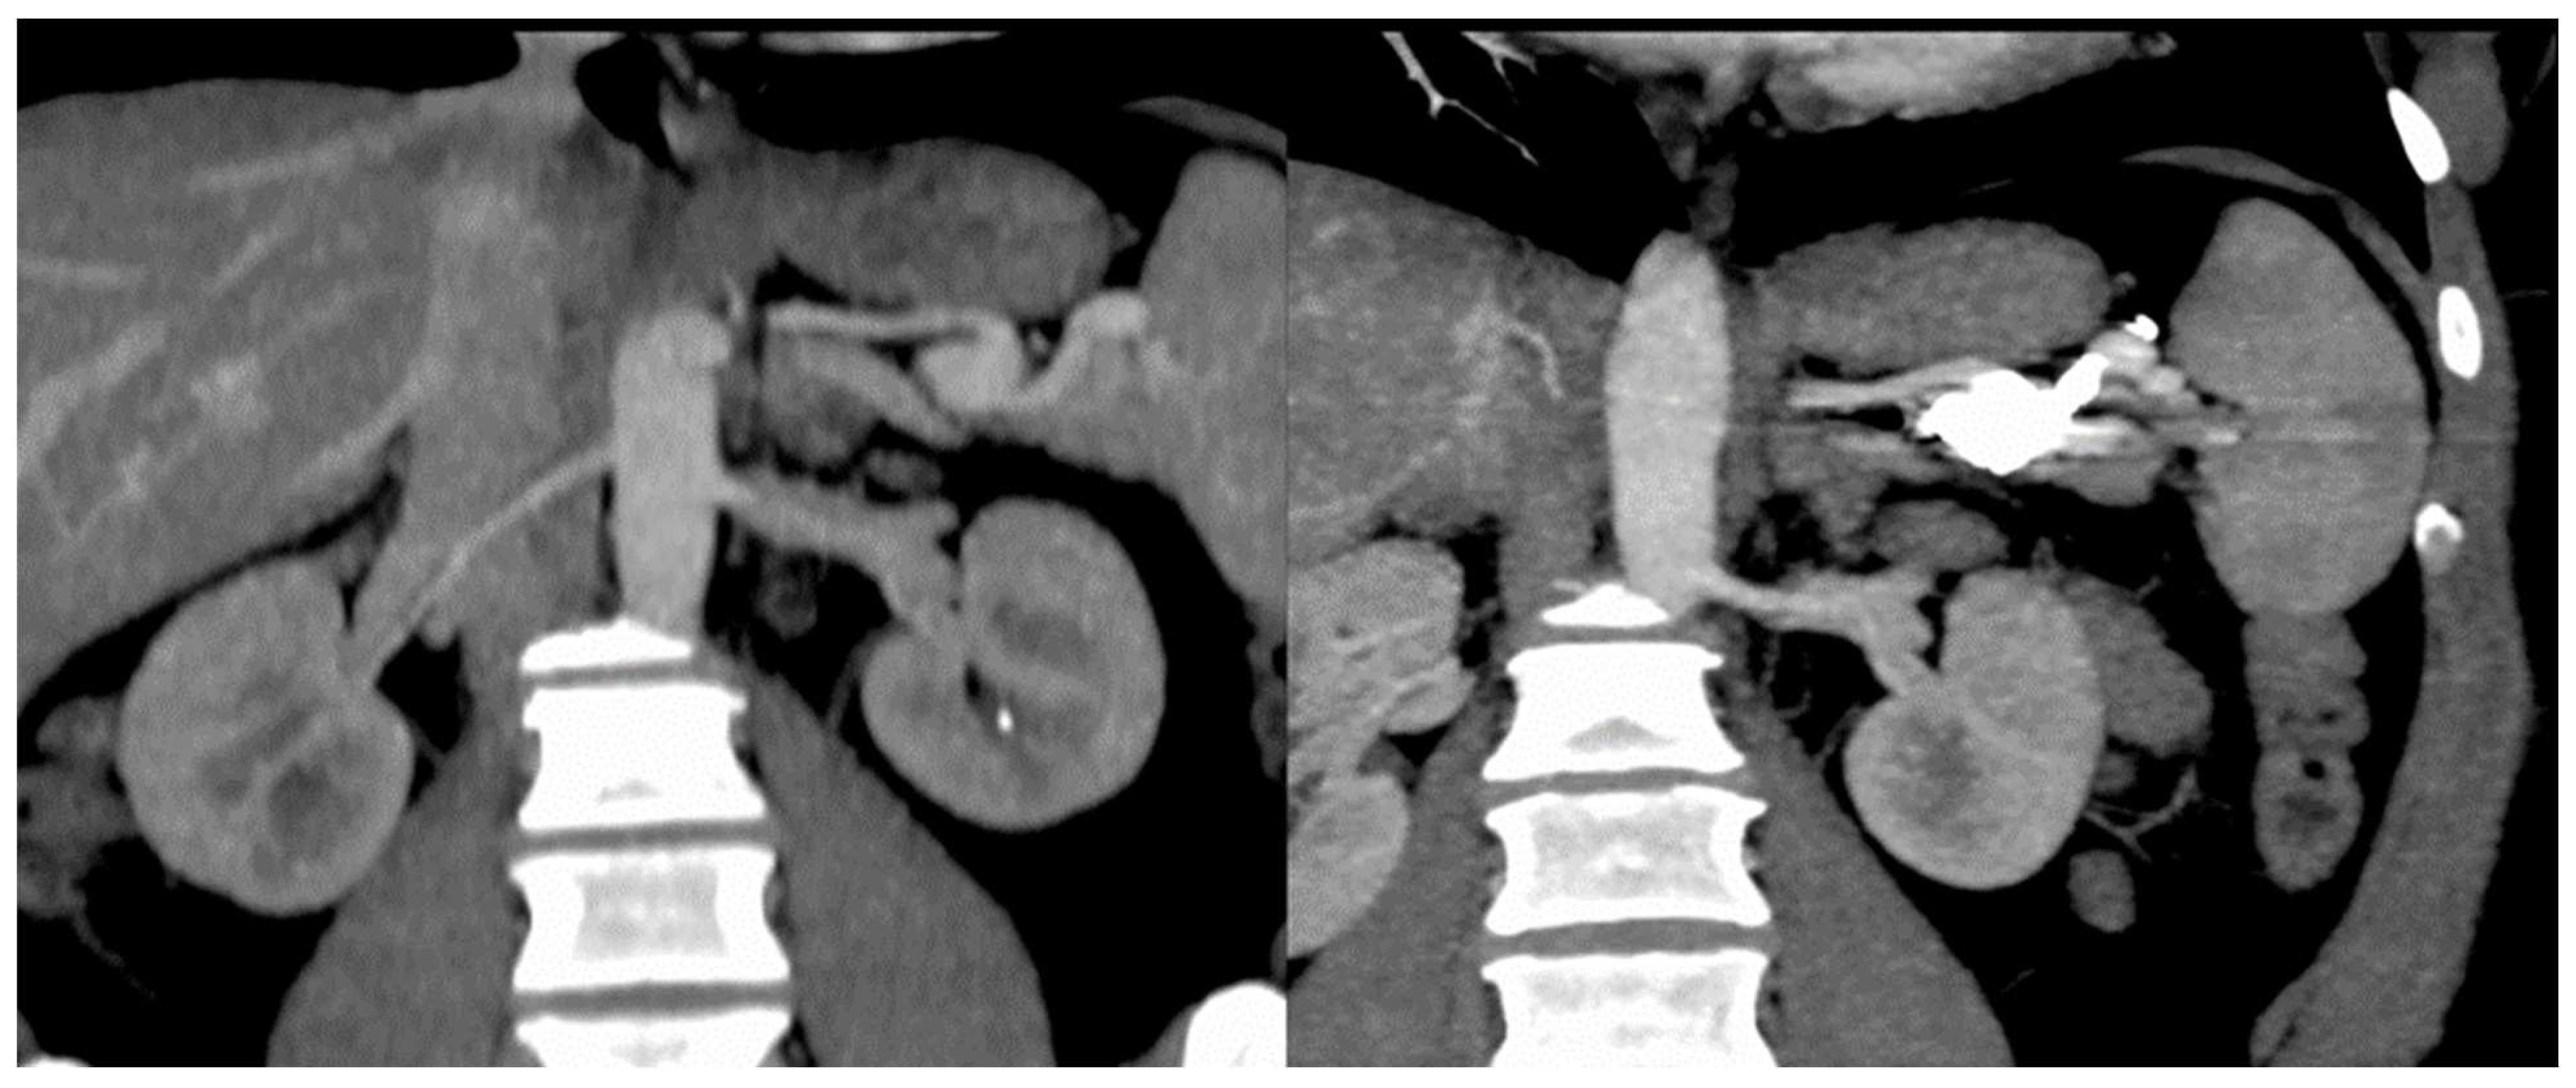

| Patient No. | 1 | 2 | 3 | 4 | 5 | 6 | 7 | 8 | 9 | 10 | 11 | 12 | 13 | 14 | Total |

|---|---|---|---|---|---|---|---|---|---|---|---|---|---|---|---|

| Hepatomegaly | + | + | + | + | + | + | + | + | + | + | + | + | − | + | 13 |

| Splenomegaly | − | − | − | − | − | + | − | − | + | − | + | − | − | − | 3 |

| Cirrhotic liver | − | + | + | − | − | − | − | − | − | + | + | + | − | − | 5 |

| HA diameter (mm) | + | 14 | 13 | − | − | 12 | 11 | 11 | 10 | 13 | 14 | + | 14 | 10 | Mean −12.2 |

| Dilated/tortuous intrahepatic artery branches | + | + | + | − | − | − | − | − | − | + | + | + | − | − | 6 |

| HA to HV shunting | + | + | + | + | + | + | − | + | + | − | + | + | + | − | 11 |

| HA to PV shunting | + | + | + | − | − | − | − | − | − | − | + | + | − | − | 5 |

| PV to PV shunting | − | + | + | − | − | − | − | − | − | − | − | − | − | − | 2 |

| Intrahepatic telangiectasis | + | + | + | + | + | + | − | + | + | + | + | + | + | − | 12 |

| Splenic artery thrombosis | + | − | + | − | − | − | − | − | + | − | − | − | − | − | 3 |

| Heterogenous enhancement on arterial phase | + | + | + | + | + | − | − | + | + | + | + | + | − | − | 10 |

| PV enlargement | − | + | + | − | − | + | − | − | + | − | + | + | − | − | 6 |

| HV enlargement | + | + | + | + | − | − | − | + | + | + | + | + | − | − | 10 |

| Collateral circulation | + | + | − | − | − | − | − | + | + | − | + | − | − | − | 5 |

| IHBD dilatations | − | + | + | − | − | + | + | − | − | + | − | − | − | − | 5 |

| Biliary cyst | − | − | − | − | − | − | − | + | − | − | − | − | − | − | 1 |

| Hemangioma | − | + | + | + | − | + | − | + | + | − | − | − | − | − | 6 |

| Nodular hyperplasia | − | + | − | − | − | − | − | − | − | + | − | − | − | − | 2 |

| Ascites | − | + | + | + | − | − | − | + | − | + | + | − | − | + | 7 |